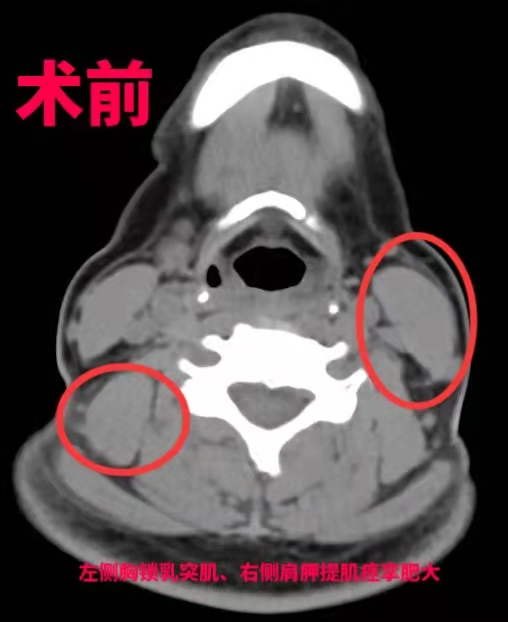

“最好的方式是手术,考虑到钟女士年轻还要负担一家老小,我们决定选择用‘超选择性神经根切断术’治疗她的痉挛性斜颈。”王向宇表示,相比于其他方式,这种术式需要在术前进行详细检查和评估,通过影像、肌电图检查、选择性肌肉阻滞等专业方法,事先找到“肇事”肌肉,在术中用最小电量反复刺激,精准找到这些“肇事”肌肉的支配神经,进行选择性的神经根切断,而不伤害其他神经和肌肉,进一步减少损伤。经过6个小时后,手术宣布成功,钟女士经过1周的恢复,“歪脖子”的问题得到了根本性解决。